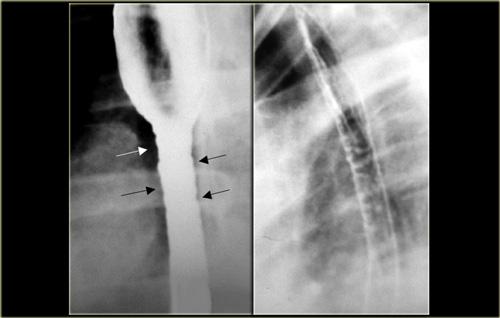

Bên trái là hình ảnh bệnh nhân có vòng ‘B’ (các mũi tên) nằm cách cơ hoành vài cm, tại đỉnh của thoát vị hoành trượt.

Lưu ý hình ảnh không thay đổi trên hai ảnh này.

Bên trái là hình ảnh nam bệnh nhân 52 tuổi với triệu chứng nuốt khó từng đợt.

Hình ảnh ngoài cùng bên trái không cho thấy bất thường, tuy nhiên thực quản đoạn xa chưa giãn căng.

Khi thực quản đoạn xa giãn căng, vòng B Schatzki rộng 13 mm (các mũi tên) gây tắc nghẽn từng đợt được hiển thị rõ tại đỉnh của thoát vị hoành (đầu mũi tên).

Bên trái là hình ảnh nam bệnh nhân 71 tuổi với triệu chứng đau ngực sau bữa ăn nhanh.

Khiếm khuyết ngấm thuốc gây tắc nghẽn ở đoạn xa (mũi tên) là một mảnh thịt đã di chuyển vào dạ dày trong quá trình thăm khám.

Hình ảnh thực quản chụp theo dõi cho thấy vòng B Schatzki (các mũi tên) là nguyên nhân gây tắc nghẽn.